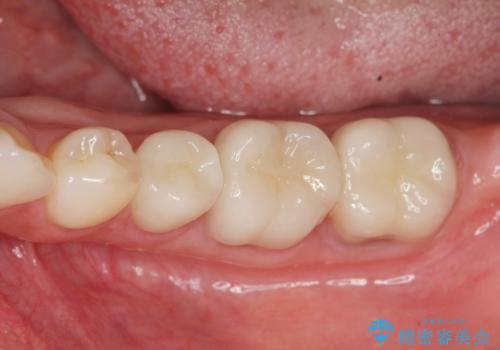

深い虫歯 歯周外科を併用した精度の高い補綴治療

- 45万円(仮歯・ファイバーコア・ジルコニアクラウン×3 歯周外科手術)費用は治療当時の料金となります